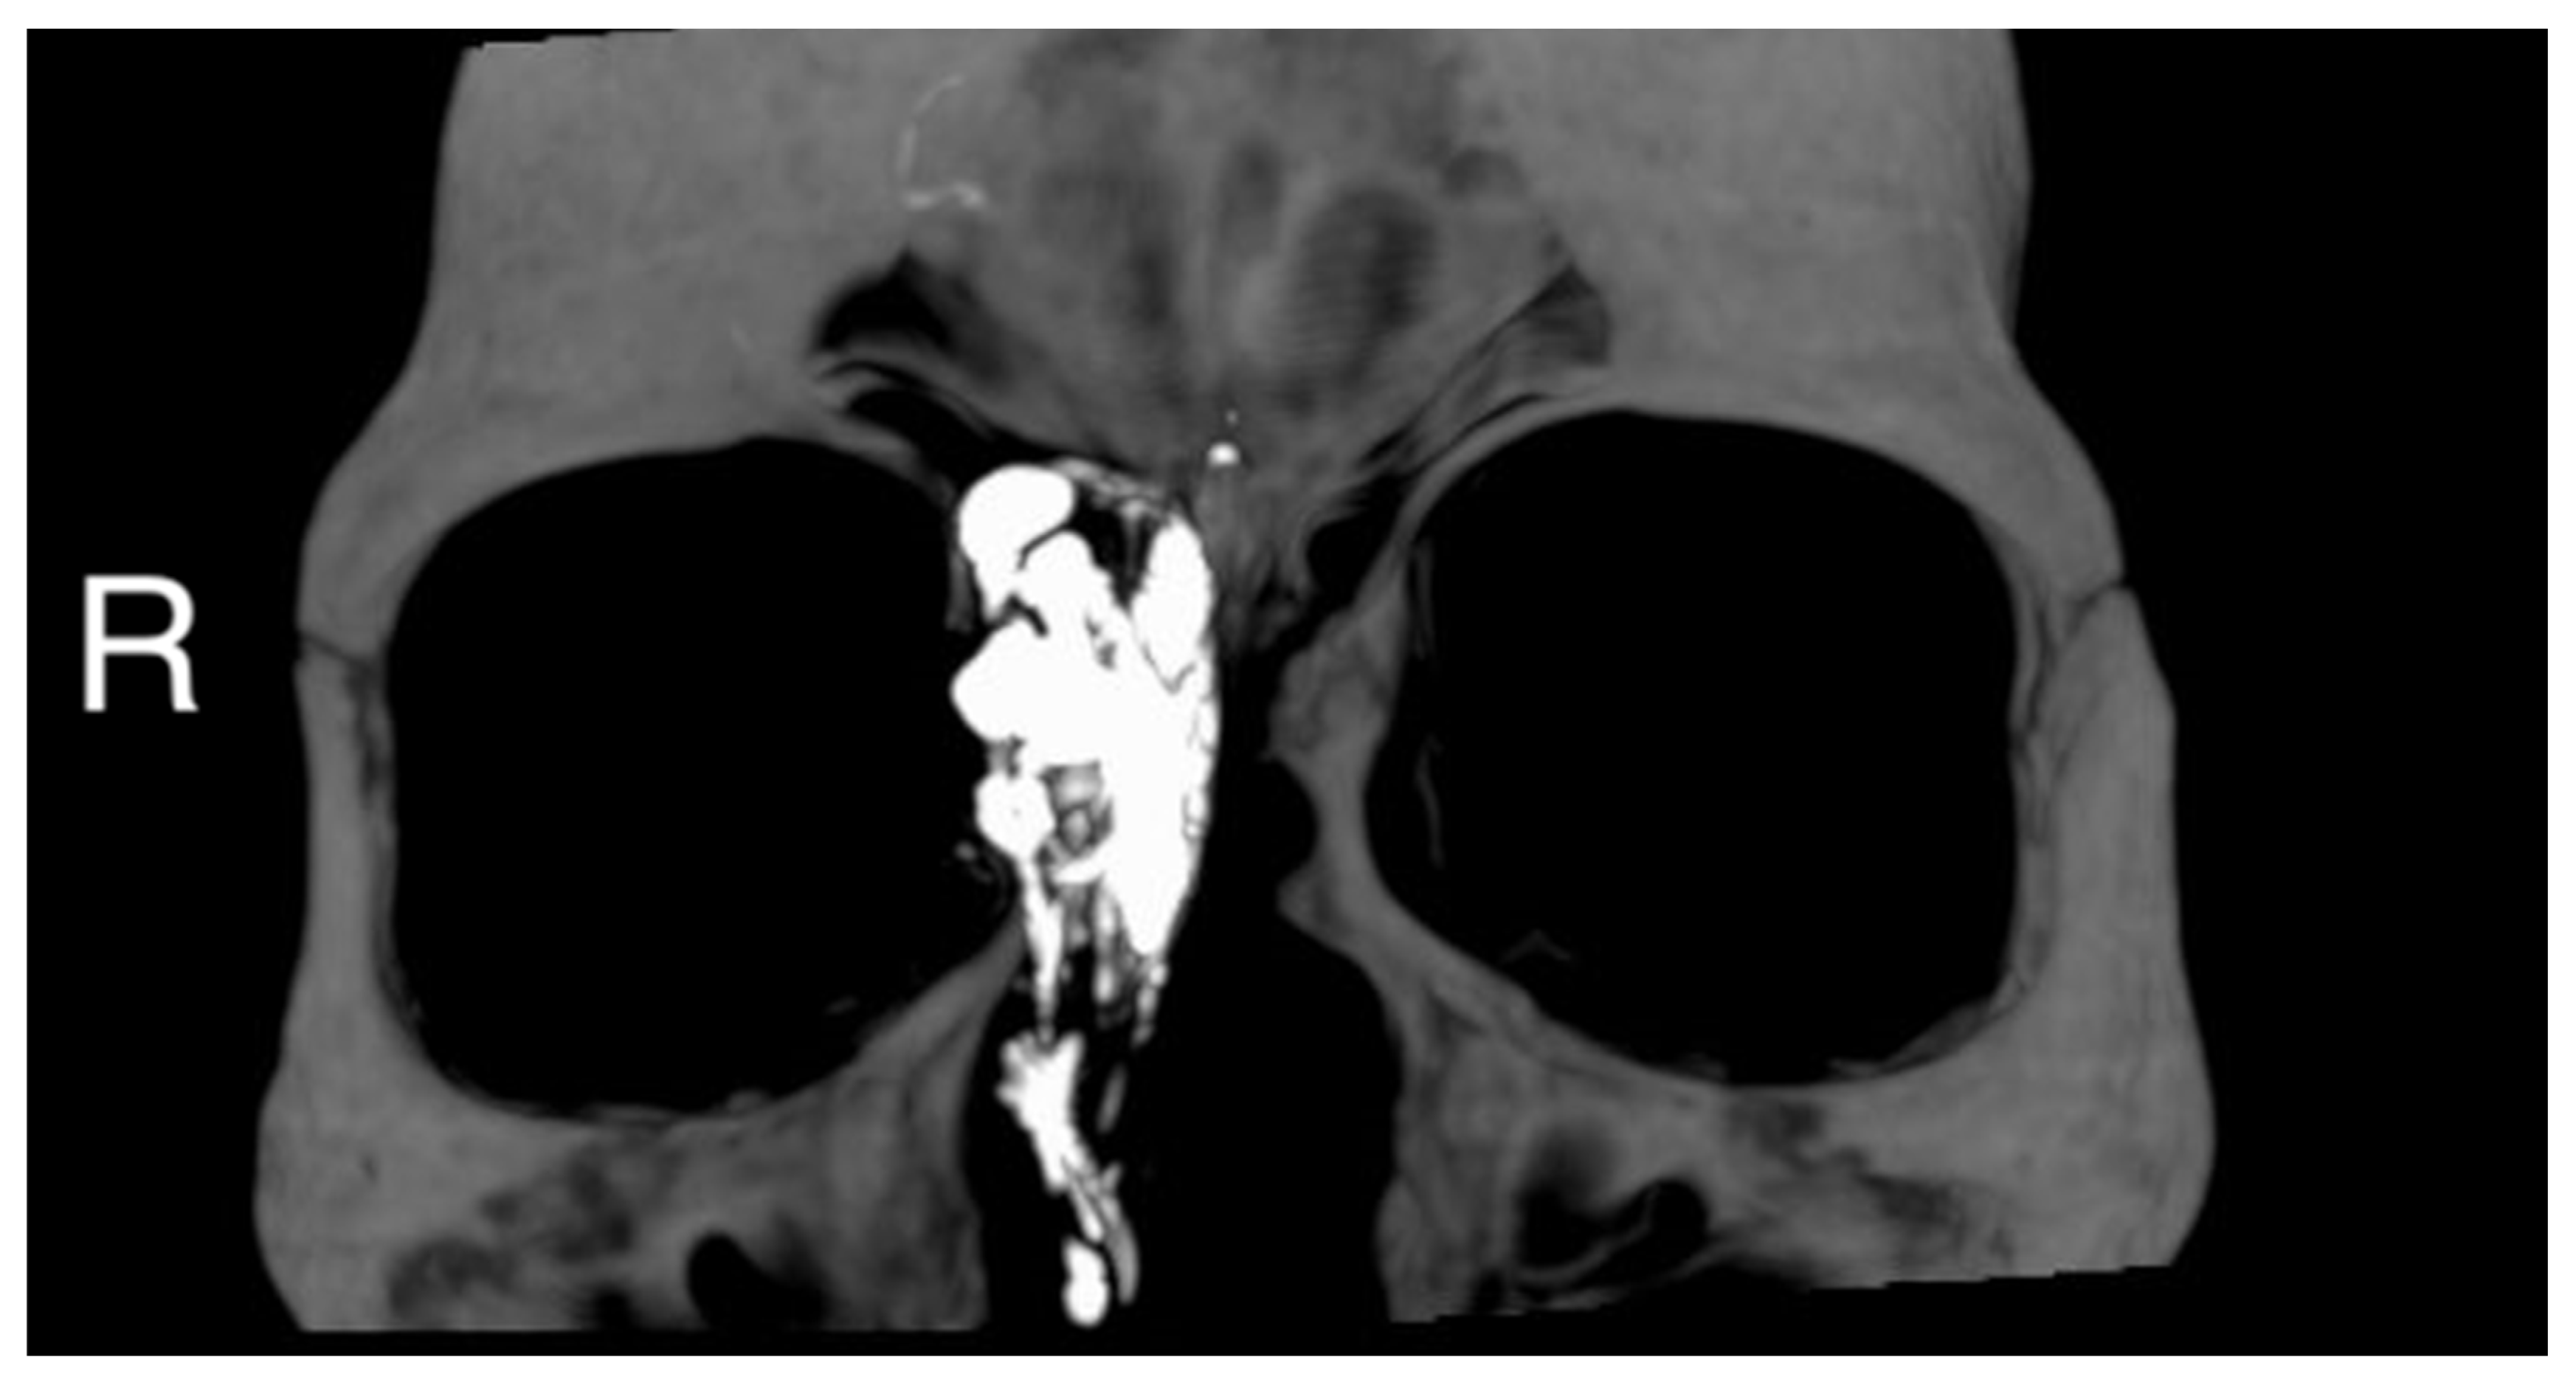

Figure 1.

(A) Preoperative MRI (Time Of Flight TOF sequence in axial view; black asterisk) and CT-scan (B) (axial view; white asterisk) (C) (coronal view; white asterisk), (D) (sagittal view; white asterisk) showing an anterior ethmoidal high vascularized tumor invading the right nasal bone and the medial wall of the right orbit. R = right, P = posterior.